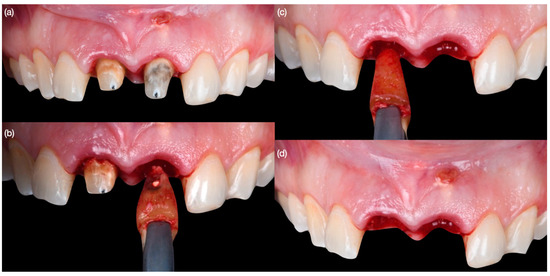

Figure 4. Atraumatic tooth extractions. (a) Crowns removed, (b) extraction of left central incisor, (c) extraction of right central incisor, and (d) both teeth extracted.

Diagnostic three-dimensional digital scans (iTero Lumina, San Jose, CA, USA) of the maxilla and mandible were taken, and a traditional facebow record (Artex Facebow, Amann Girrbach, Koblach, Austria) was obtained. Printed models (Phrozen Sonic Mini 8K Resin 3D Printer, Phrozen Technology, Hsinchu City, Taiwan) were then fabricated and mounted on a semi-adjustable articulator (Artex CR, Amann Girrbach, Koblach, Austria). A diagnostic wax-up was performed and mounted in the articulator. The patient also received an intra-oral mock-up with a putty index guide (Elite P&P, Zhermack, Badia Polesine, Italy). An initial CBCT scan and the intra-oral scan were used to digitally plan the implant placement (Exocad DentalCAD, Darmstadt, Germany) and print the surgical guide (Phrozen Sonic Mini 8K Resin 3D Printer, Phrozen Technology, Hsinchu City, Taiwan) (Figure 3). Atraumatic tooth extractions were performed for both maxillary central incisors with the use of a periotome (Anterior Straight PT6, Hu-Friedy, Chicago, IL, USA) and forceps (Upper Anterior Atlas FAF1IS, Hu-Friedy, Chicago, IL, USA), only providing vertical forces, and avoiding any horizontal force (Figure 4). The extraction sockets were cleaned thoroughly with curettes (Universal Curette, Hu-Friedy, Chicago, IL, USA), and the abscess cavity was irrigated with saline solution and chlorohexidine to flush out all the debris and blood. The 3D-printed surgical guide was placed in position, osteotomies were performed, and two implants (3.5 mm diameter; 11.50 mm length, Helix GM, Neodent, Basel, Switzerland) were placed at the planned depth (Figure 5 and Figure 6). An autogenous soft tissue graft was harvested from the palate and positioned on the facial surface of the maxillary left side implant using polyethylene sutures. Interim abutments (Gm Temporary Abutments for Crown, Neodent, Basel, Switzerland) were placed with screw-retained non-occluding interim crowns (Figure 7). The patient had regular follow-up evaluations at 2, 4, 7, and 10 weeks, and at 3 and 4 months, after the implant placement. The provisional restoration was recontoured at week 10, and new sets of interim restorations were made at 3 and 4 months (Figure 8). The patient and clinicians were fully satisfied with the contour obtained with the last set of provisional restorations at 4 months, and it was decided to continue the final stage of the treatment (Figure 9).